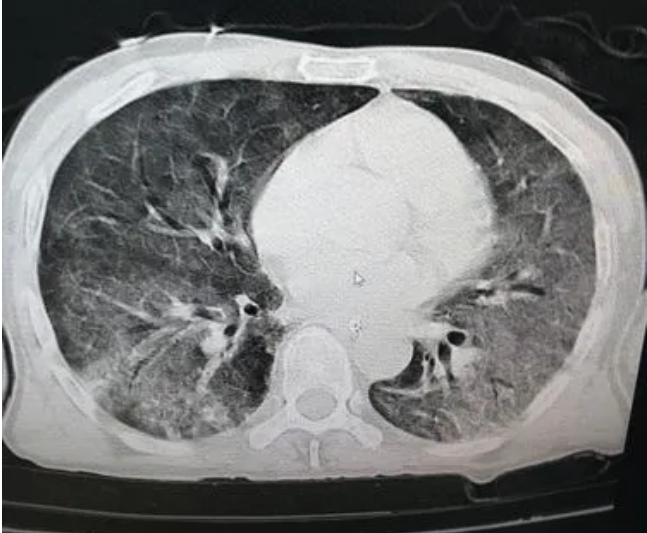

大(dà)部分(fēn)甲流患者都(dōu)是(shì)輕症,但(dàn)也(yě)有(yφ"ǒu)患者可(kě)能(néng)出現(xiàn)腦(nǎo)炎、腦(nǎo)膜炎¶±✘β、心肌炎、心包炎等并發症,最常見(jiàn)的(de)并發症是(shì)病毒性肺炎,甚至是(shì®γ)“白(bái)肺”。

因為(wèi)病毒進入人(rén)體(tǐ)後,會(huì)激發人♥↕§(rén)體(tǐ)的(de)免疫反應,體(tǐ)內(nèi)的(de)抗體(tǐ)→≤會(huì)被激發起來(lái)與病毒做(zuò)“鬥争”,在此過程中,機(jī)體(tǐ)裡(lǐ)會(huì)有(yǒu)大($∑dà)量液體(tǐ)與細胞滲出,填充在肺泡裡(lǐ),影(yǐng)像學表現(xiàn)✔✔為(wèi)大(dà)片的(de)白(bái)色,這(zhè)就(jiù)是(s♠×hì)所謂的(de)“白(bái)肺”。白(bái)色陰影(yǐng)越多(duō),說(shuō)明(míng)肺部炎症±®<∏和(hé)感染越重,病人(rén)會(huì)出現(xiàn)很(hěn)嚴重的(de)呼吸↕γ衰竭。